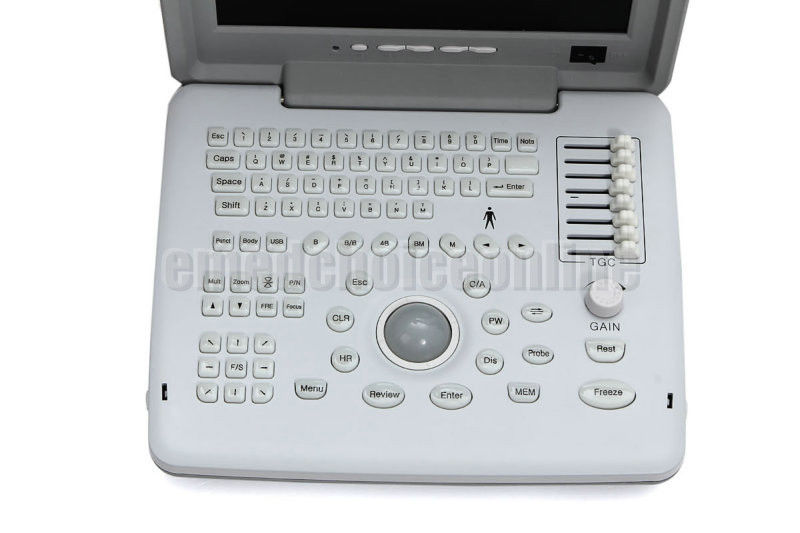

Full Digital Ultrasound Ultrasonic Scanner System 7.5 Mhz Linear Probe 3D image 190891058744

Model: RUS-9000B

Image mode: B, B/B, 4B, B+M, M

Local zoom: 2 times local zoom in real time

Display: 10-inch SVGA high resolution monitor